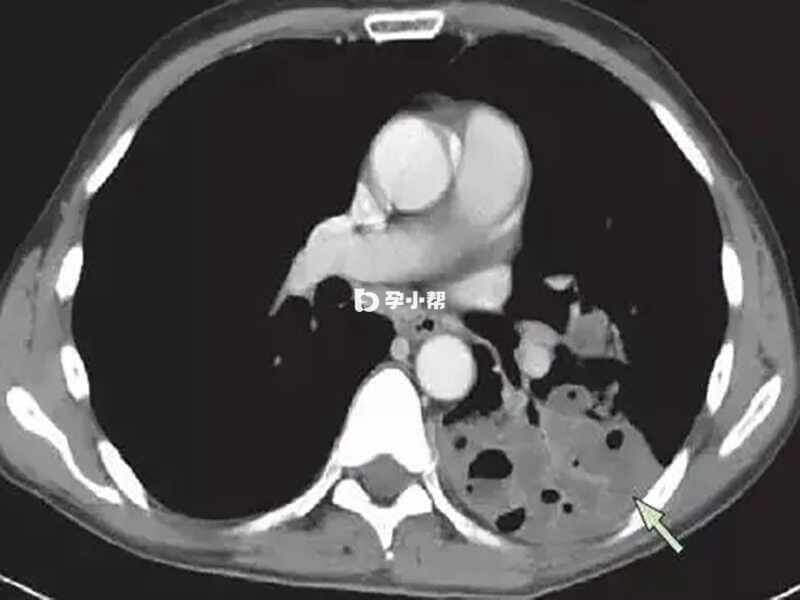

1. 肝功能检查:对黄疸、乏力、肝区痛等丙型肝炎相关症状患者,均应进行肝功能检查。此项检查为静脉血检查结果,指尖釆血、耳垂采血均无效;患者需在前一晚12点之后不再进食和饮水,次日到医院抽取静脉血进行检测,检查当天早上应避免剧烈活动;尽量避免在静脉输液期间或在用药4小时内做肝功能检查;2. 抗-HCV检测:丙型肝炎病毒感染的高危人群、有乏力等临床表现时,或者不明原因的转氨酶增高,应检测血清中抗-HCV。此项检查为静脉血检查结果,指尖釆血、耳垂采血均无效;如果抗-HCV阳性,应进一步检测血清或血浆或HCV核心抗原(检测不可进行时),以明确是否体内有丙型肝炎病毒存在;3. 检测:抗-HCV阳性,或者怀疑有急性的丙型肝炎病毒感染而抗-HCV阳性时,应检测。阳性是丙肝病毒感染和复制的直接标志。定量检测适用于判断患者是否正处于HCV疾病发病期、抗病毒治疗前基线病毒载量分析、以及抗病毒治疗过程中及治疗结束后的应答评估;4. HCV基因型和变异检测:目前治疗丙型肝炎病毒的药物对已知的基因型都有效,仅仅部分治疗方案需要根据HCV的基因型来决定药物选择。因此,采用基因型特异性直接抗病毒药物(s,DAAs)治疗的感染者,需要先检测基因型;5. 瞬时弹性成像(TE):TE是一种超声弹性成像技术,通过检测肝组织硬度可评估肝纤维化分期,具有无创性,快速等优点。TE对慢性丙型肝炎肝纤维化[1]分期的诊断较为可靠,对肝硬化的诊断更准确;6. 影像学检查:目前常用的影像学诊断方法包括腹部超声检查(US)、CT和磁共振(MRI或MR)等,可以帮助监测慢性丙型肝炎肝硬化的临床进展、发现和鉴别肝硬化腹水等并发症,以及原发性肝癌(HCC)的筛查和诊断。